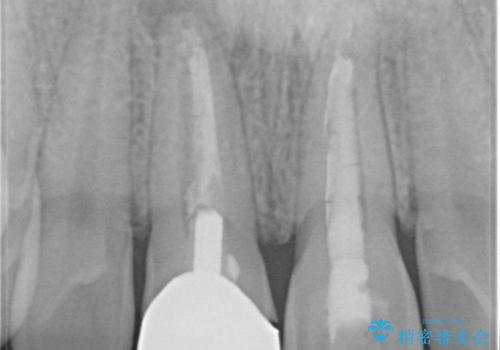

特に右上の前歯の膿は大きくなって歯ぐきから排膿している状態でした。(フィステルといいます)

二本とも神経の治療のやり直し(再治療)を行ってからセラミックを入れています。

神経の治療をした歯は変色してくるため、歯ぐきから歯の根が透けて見えるのは治療はむずかしいです。